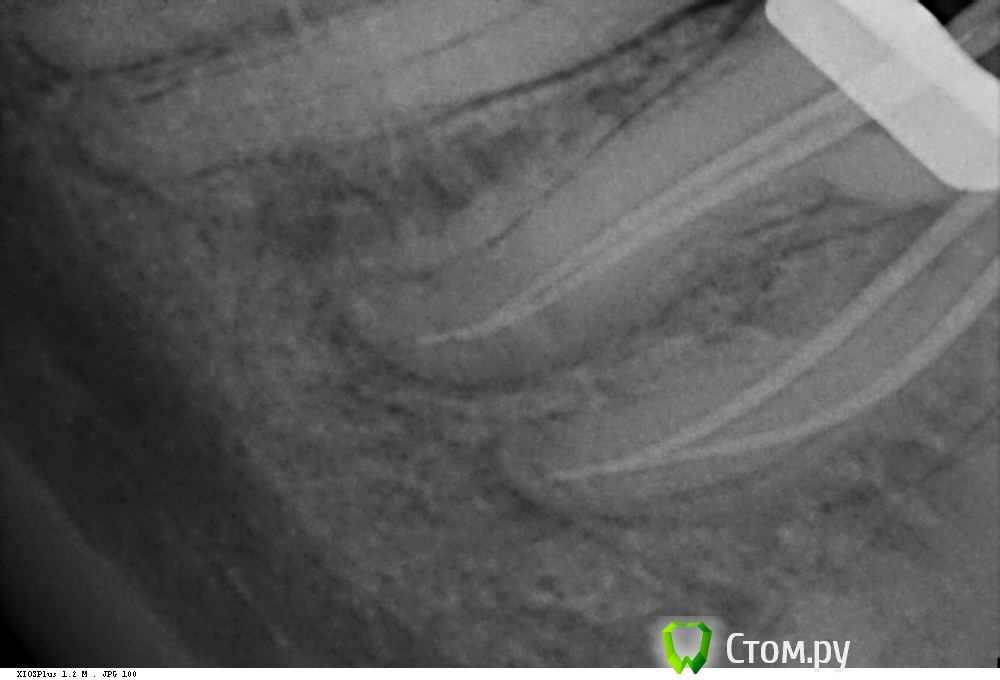

Shaid Опубликовано 29 января, 2014 Автор Поделиться Опубликовано 29 января, 2014 (изменено) Рис.1 Пульпит 2.5. Ничего необычного нет, просто понравился снимок) Возможно, кому-то покажется, что каналы перерасширены?Рис.2,3 Тоже пульпит пятерки. Тот случай, когда спредер залезает в канал, а 15 штифты - нет, гнутся , в результате чего картинка вызывает ассоциации, будто в каналы засунули по две дренажной трубки из хирургии. Изменено 29 января, 2014 пользователем Shaid Ссылка на комментарий